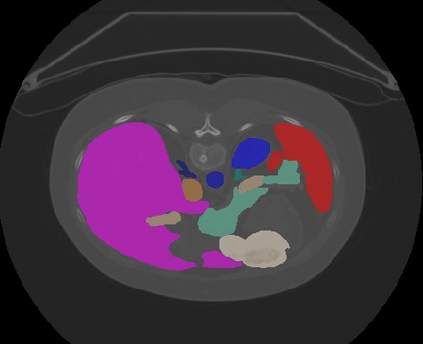

Transformers, the default model of choices in natural language processing, have drawn scant attention from the medical imaging community. Given the ability to exploit long-term dependencies, transformers are promising to help atypical convolutional neural networks (convnets) to overcome its inherent shortcomings of spatial inductive bias. However, most of recently proposed transformer-based segmentation approaches simply treated transformers as assisted modules to help encode global context into convolutional representations without investigating how to optimally combine self-attention (i.e., the core of transformers) with convolution. To address this issue, in this paper, we introduce nnFormer (i.e., Not-aNother transFormer), a powerful segmentation model with an interleaved architecture based on empirical combination of self-attention and convolution. In practice, nnFormer learns volumetric representations from 3D local volumes. Compared to the naive voxel-level self-attention implementation, such volume-based operations help to reduce the computational complexity by approximate 98% and 99.5% on Synapse and ACDC datasets, respectively. In comparison to prior-art network configurations, nnFormer achieves tremendous improvements over previous transformer-based methods on two commonly used datasets Synapse and ACDC. For instance, nnFormer outperforms Swin-UNet by over 7 percents on Synapse. Even when compared to nnUNet, currently the best performing fully-convolutional medical segmentation network, nnFormer still provides slightly better performance on Synapse and ACDC.